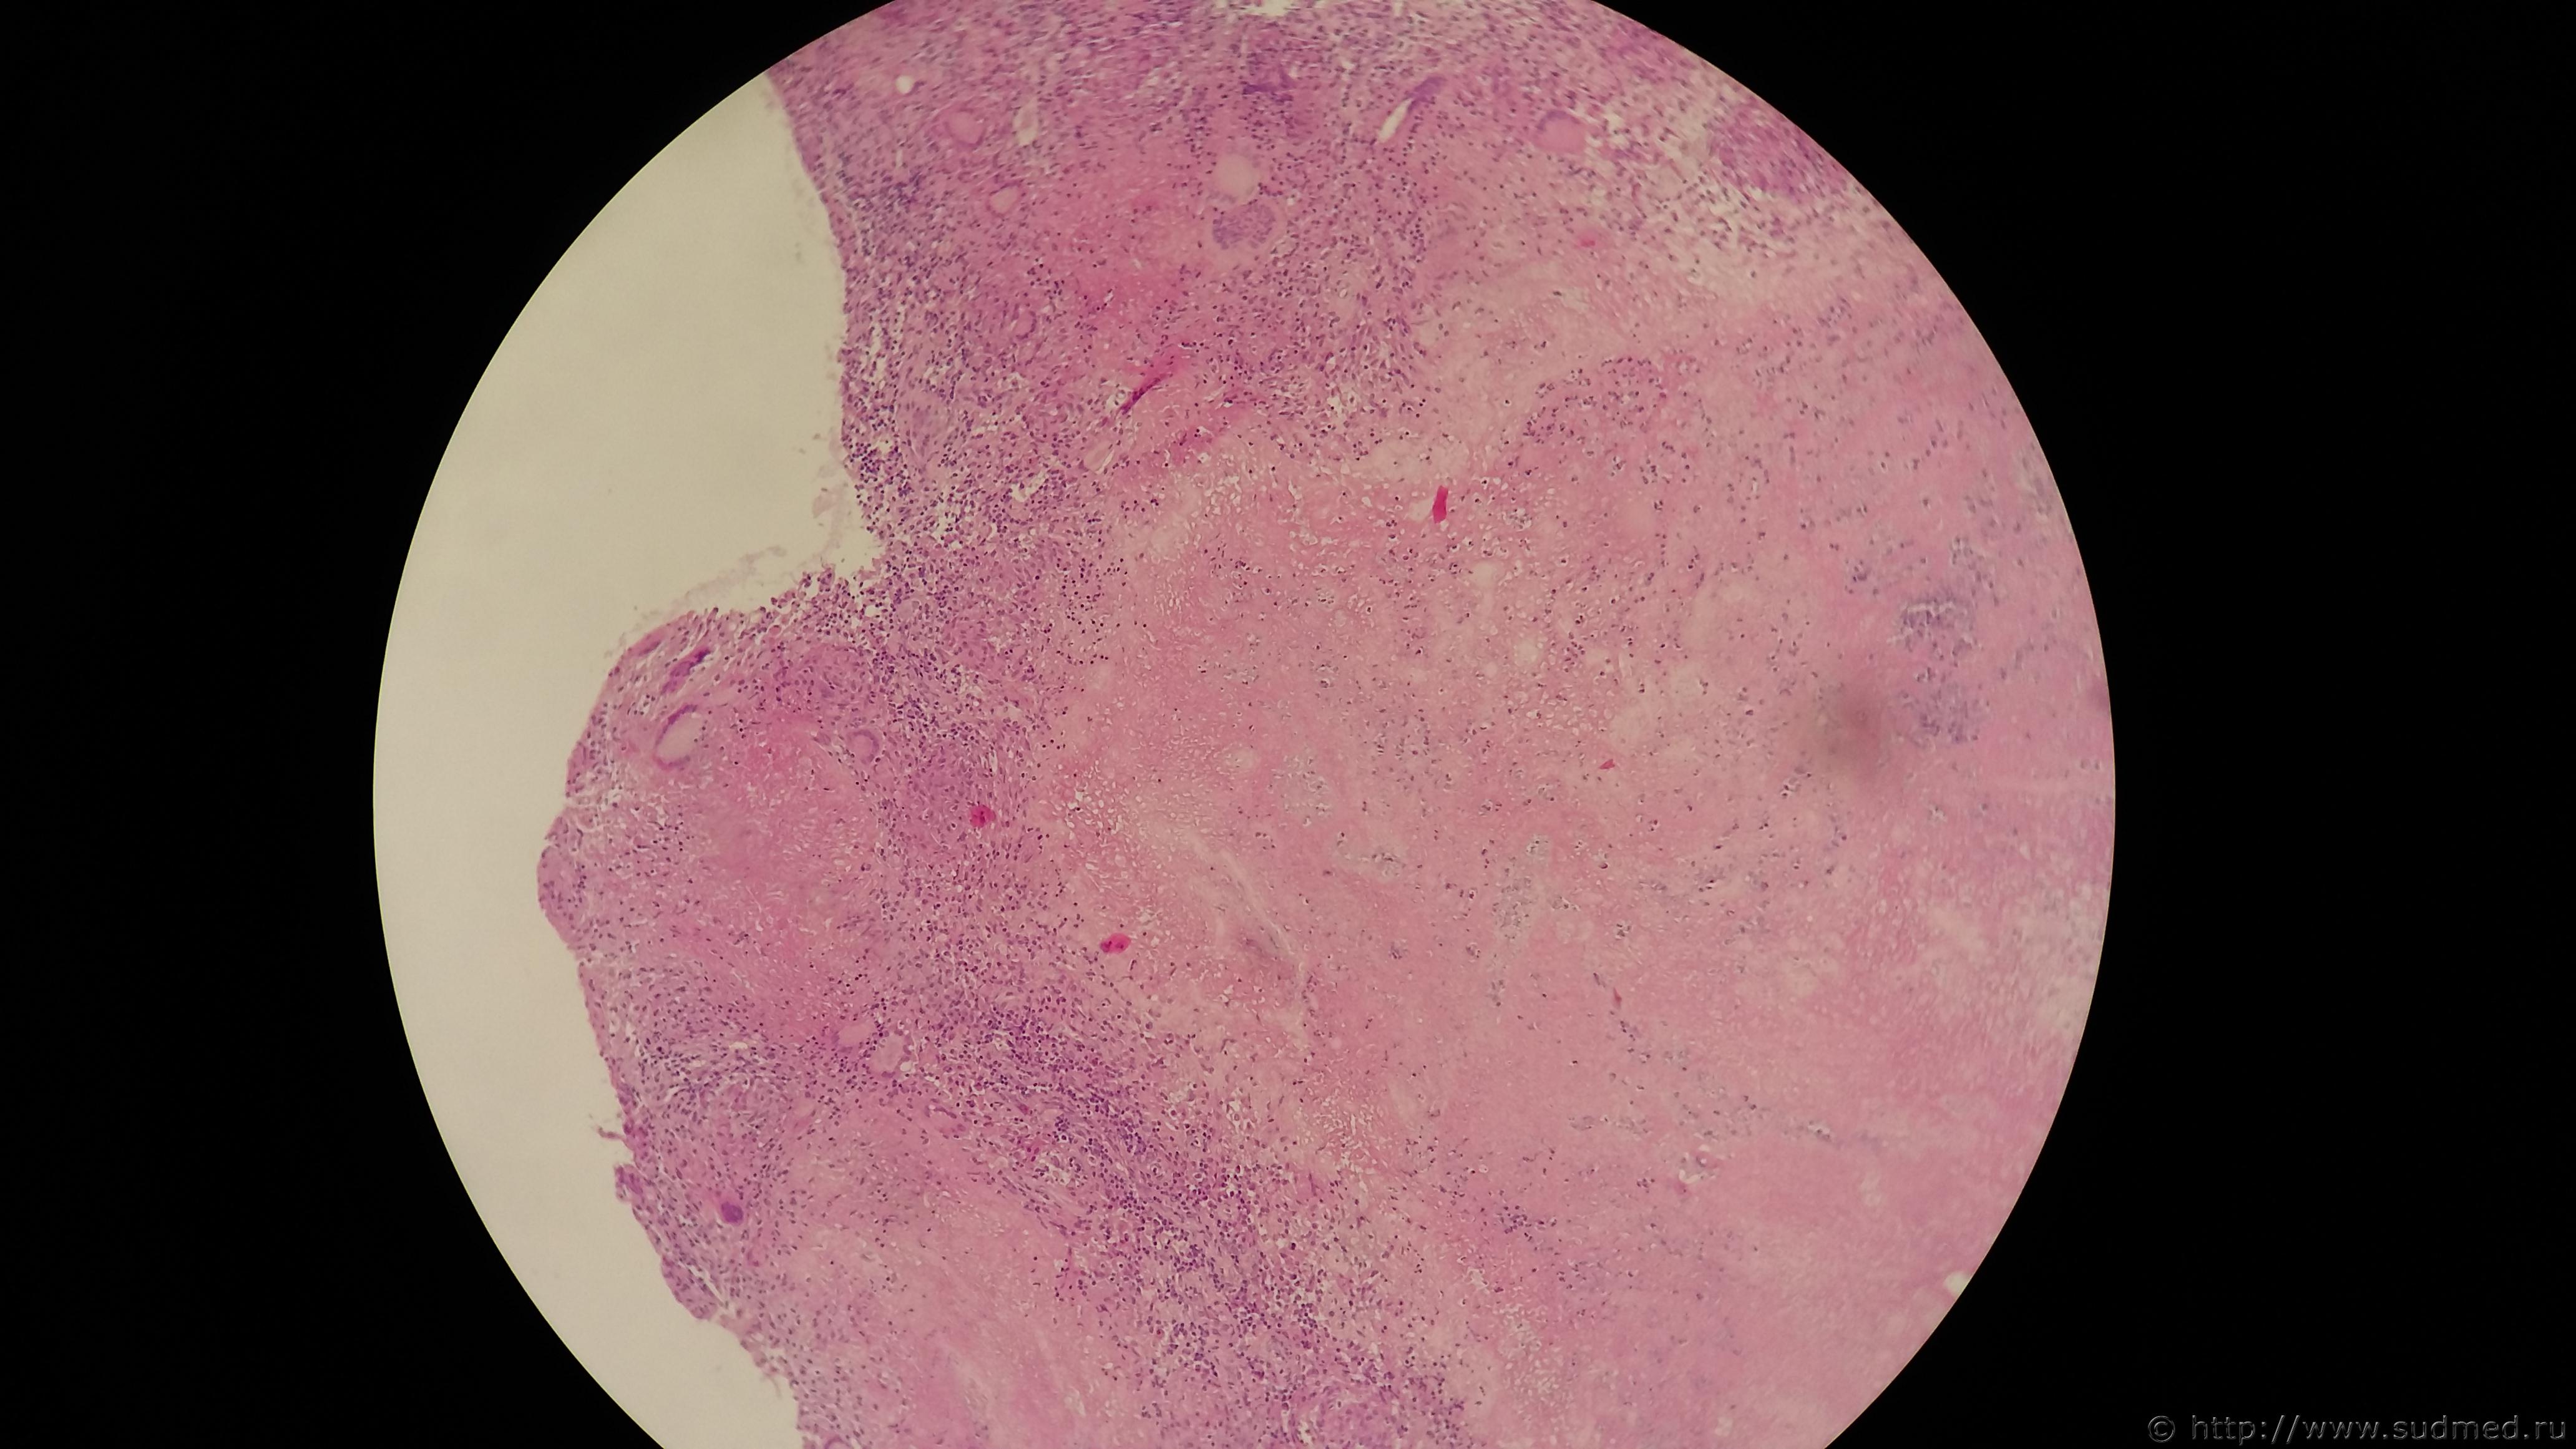

Женщина приблизительно 30 лет потеряла сознание дома.

Она была доставлена в больницу скорой помощью - остановка сердца и дыхания.

Ростом 172 см и 146 кг.

Подкожное кровоизлияние диаметром 4,5 см наблюдалось в эпигастральной области.

Левый яичник был заметно опухшим, а общий вес матки и правого яичника составлял более 13,0 кг. Была обнаружена левая яичниковая опухоль, состоящая из серозных и муцинозных кист. Не было метастазы других органах.

Причиной смерти считается нарушение кровообращения - асцит и опухоль цистаденома яичника.